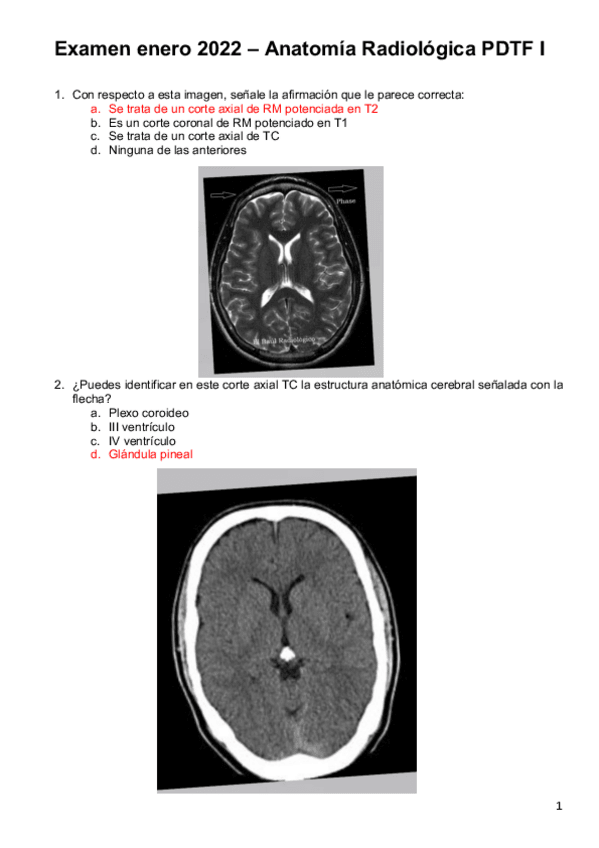

He publicado nuevos examenes de 2º PROCEDIMIENTOS DIAGNOSTICOS Y TERAPEUTICOS FISICOS I: Examen-enero-2022-Anato-Rx.pdf